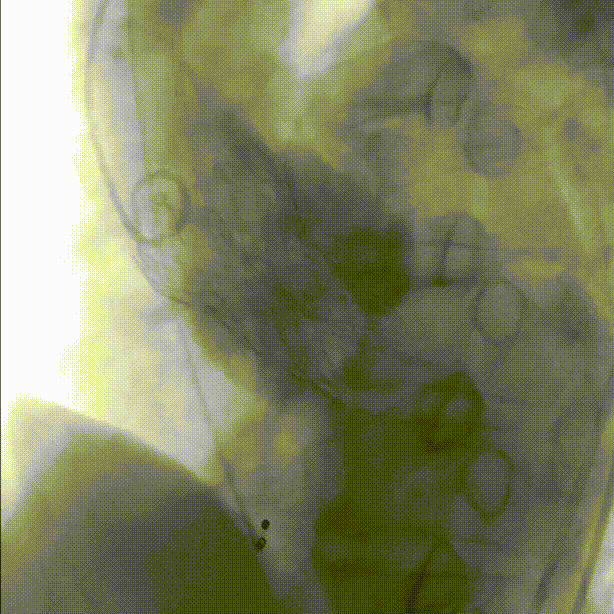

最终根部造影:无反流,冠脉灌注良好:

美敦力Evolut PRO植入术后,最终根部造影,未见反流,冠脉灌注良好,手术结束。